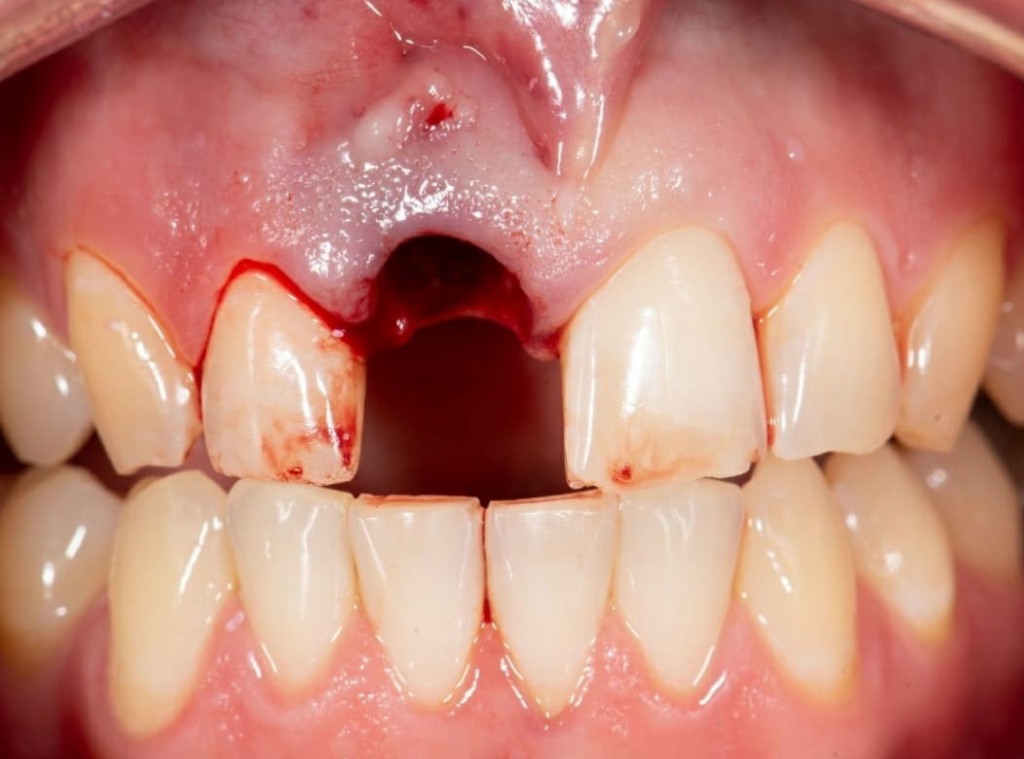

Имплантация AnyRidge во фронтальном отделе.

Пациент обратился с жалобами на эстетический вид центрального резца, небольшую подвижность и систематически появляющийся свищевой ход над зубом.

На КТ была обнаружена трещина корня, не позволяющая вылечить зуб. Было принято решение об удалении зуба с одномоментной имплантацией. Коронковую часть временного зуба восстановили из родного зуба пациента, предварительно отреставрировав его перед установкой.